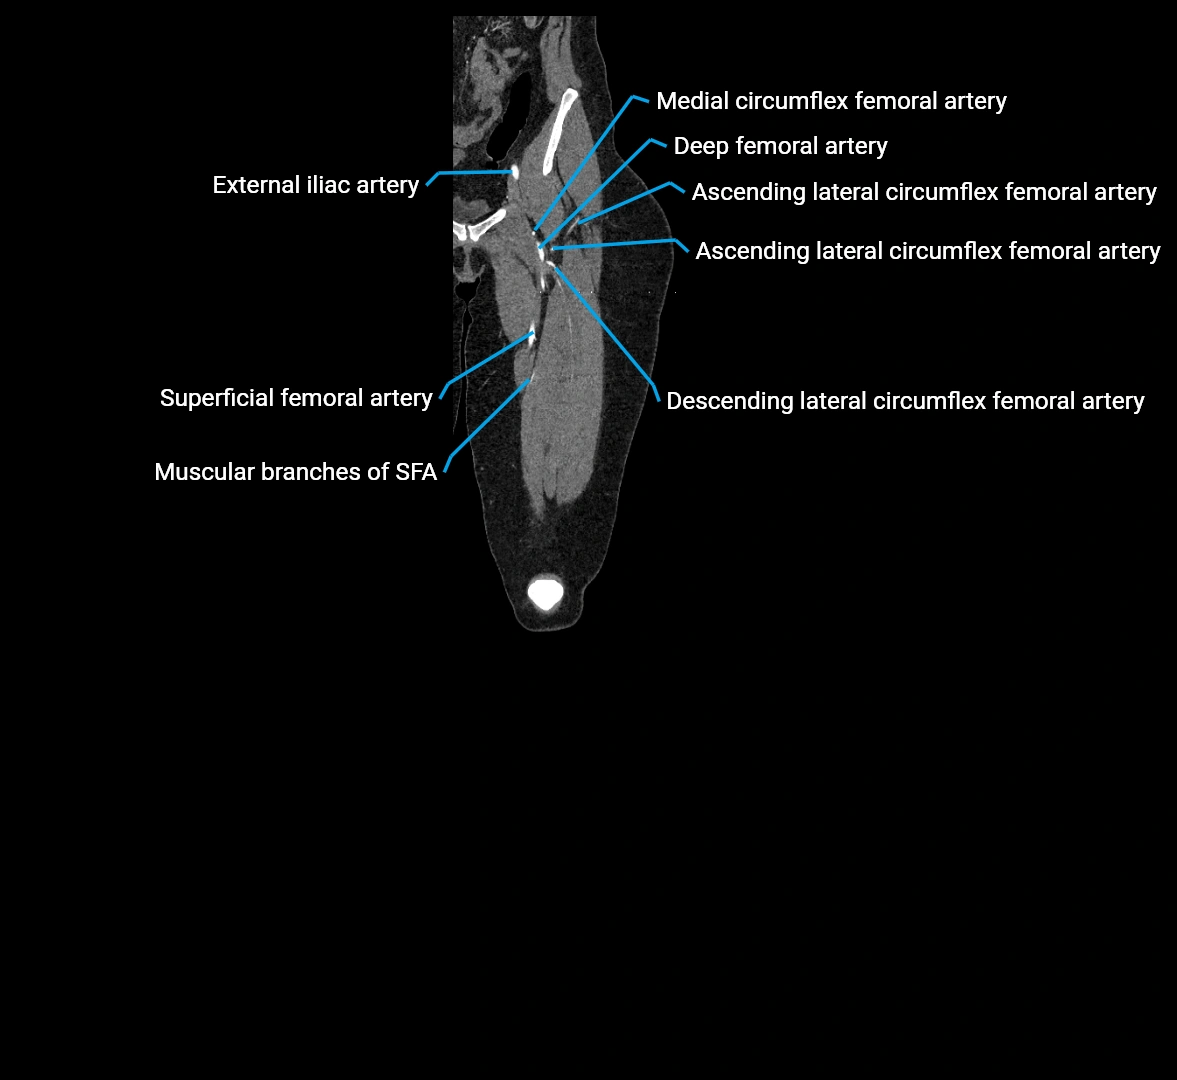

Contrast-enhanced CT (CTA):

• Gold standard for abdominal aortic imaging

• Provides excellent detail of lumen, wall, aneurysm, thrombus, and branch vessels

• Multiplanar and 3D reconstructions help in aneurysm measurement, stent graft planning, and dissection evaluation